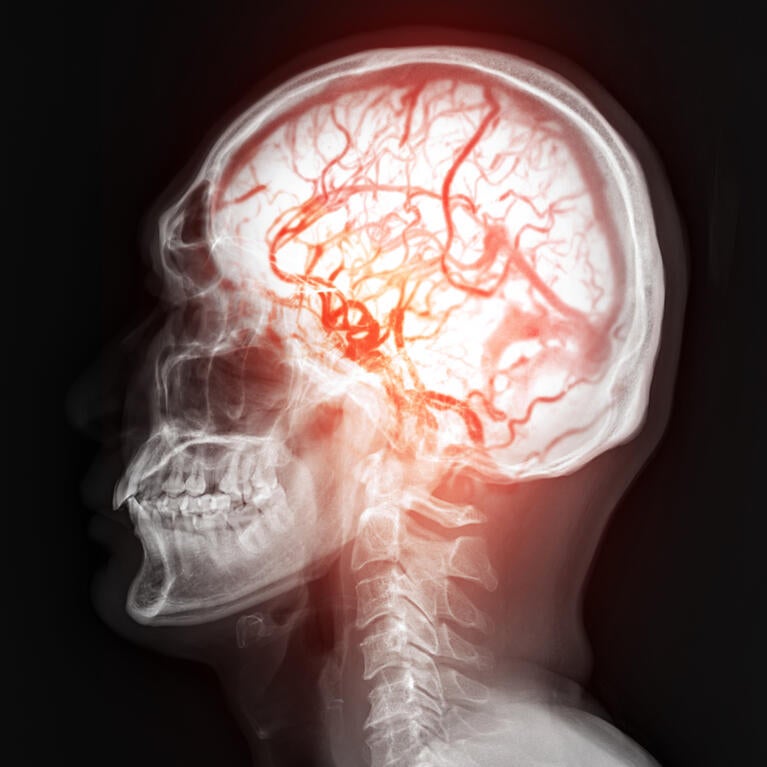

The communication network in the developing brain builds when neurons partner up to form contact points called synapses, allowing signals to pass form one cell to another. At the same time, a web of blood vessels builds the brain’s life support system, delivering oxygen and nutrients and controlling what can enter the brain. The protein Adgrl2 acts...